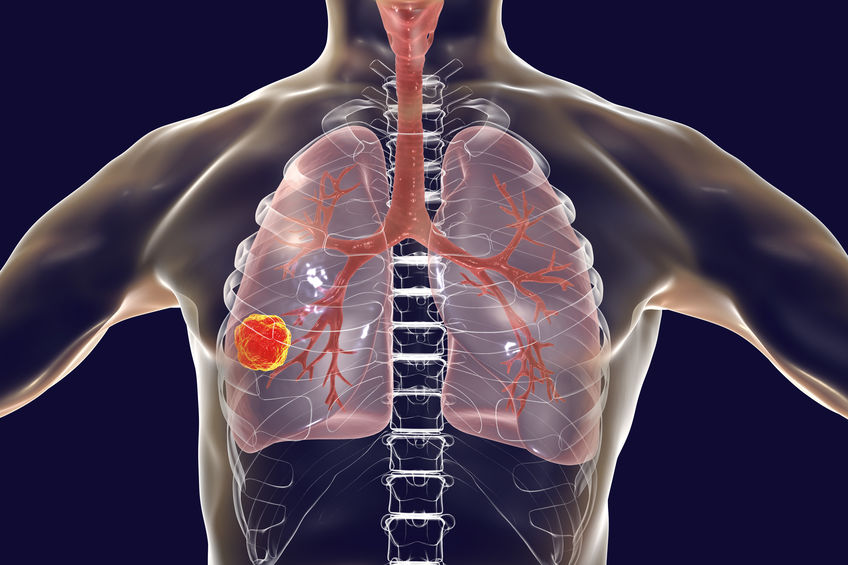

作為一種新興的方法,免疫治療肺癌逐漸得到越來越多患者的認可,相比起傳統的治療手段,其透過調節患者自身免疫系統的功能,説明患者抵抗肺癌細胞的生長和擴散,優勢在於副作用更少。alk 肺癌治療使用這種方法效果不錯,但是並非意味所有肺癌患者都適合接受免疫治療。

適合選擇免疫治療肺癌的患者病程通常已經晚期,免疫治療對於晚期肺癌患者的效果相對較好,因為晚期肺癌患者的免疫系統已經受到抑制,這種治療手段的優勢在於能夠説明患者恢復部分免疫功能,增強對腫瘤的抗擊能力。

其次,適合免疫治療肺癌的患者往往具有較高的腫瘤突變負荷,因為腫瘤突變負荷越高,腫瘤細胞就越容易被免疫系統識別並攻擊。適合免疫治療的肺癌患者還有PD-L1陽性的患者。因為這類肺癌患者通常對免疫治療更為敏感,免疫檢查點抑制劑可以阻斷PD-L1與其受體PD-1的結合,從而啟動免疫系統攻擊腫瘤細胞。

以上介紹的幾類患者適合免疫治療肺癌這種方法,醫生亦會評估身體狀況,只有具備一定的身體狀況和耐受性才推薦。雖然副作用相對較少,但是免疫治療仍然會引起如疲勞、皮疹、食欲不振等不良反應。